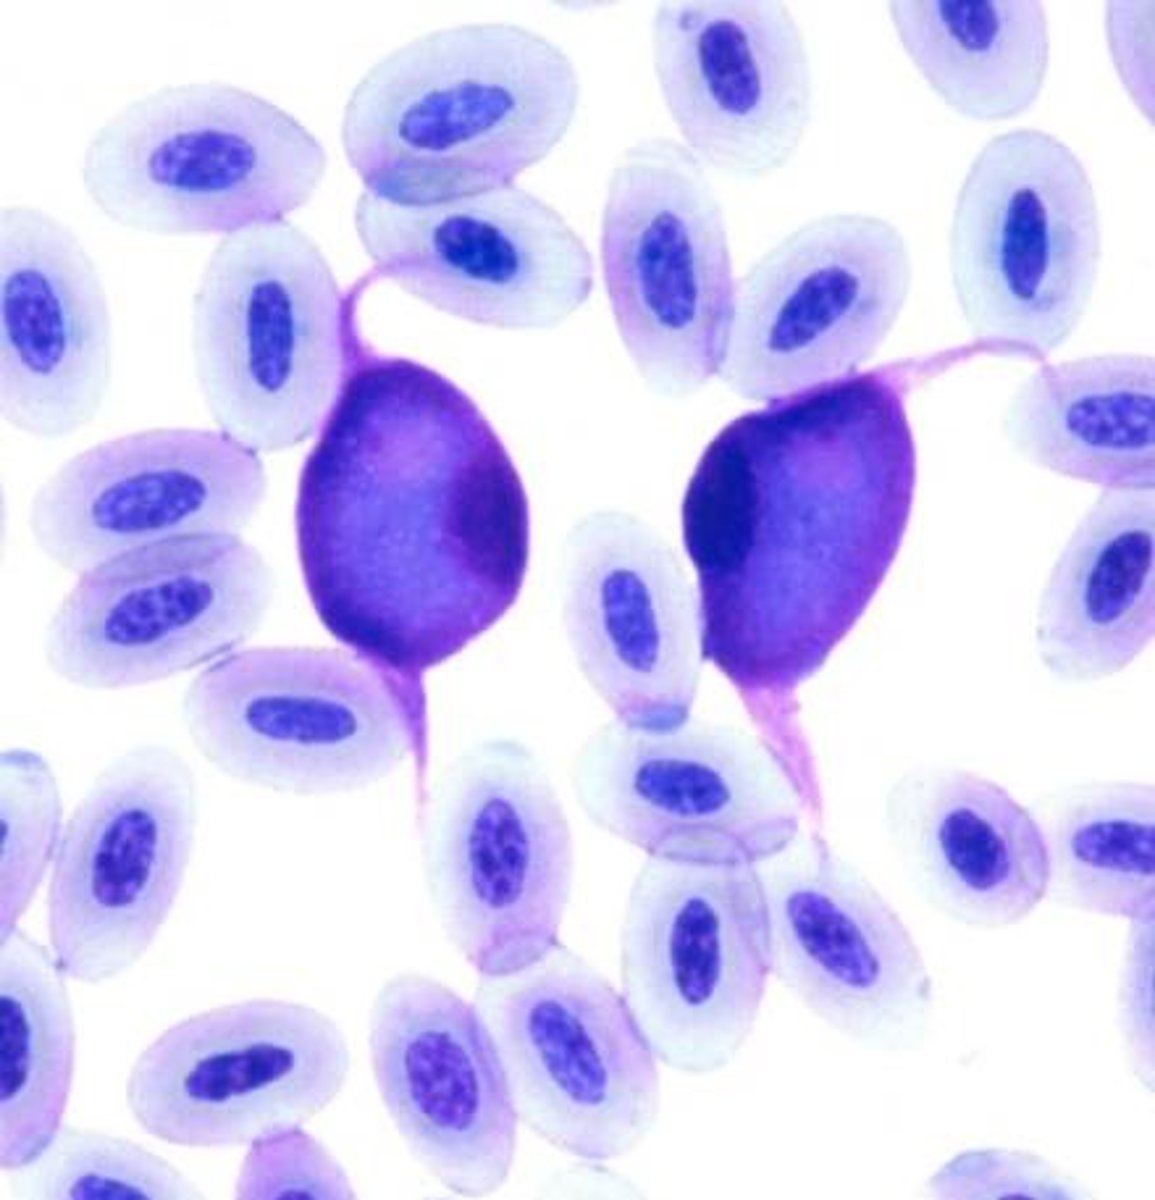

erythrocyte

avian or reptile

organelle breakdown artifact on exotic RBC

exotic

hint: not clinically significant

degenerative organelle artifact on exotic RBC

exotic

small punctate, variably sized, clear vacuoles that are not clinically significant

exotic polychromatophils

exotic

slightly rounder

basophilic cytoplasm